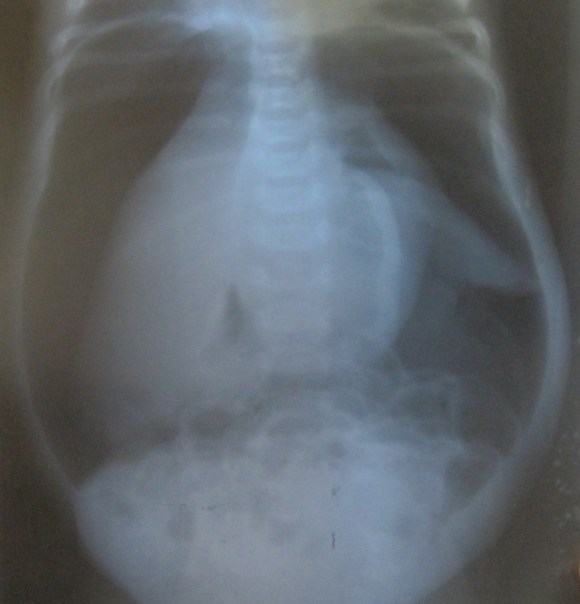

Categories Medical Surgical trauma Uncategorized Air in the wrong places Post author By hicksblmedical Post date June 28, 2020 No Comments on Air in the wrong places Quite an ‘airy experience. subcutaneous in the pleural cavity in the skull – we didn’t have a viewing box in the abdomen in the male genitals Barry Hicks Tags abdomen, Chest, genitals, head tauma, X-rays